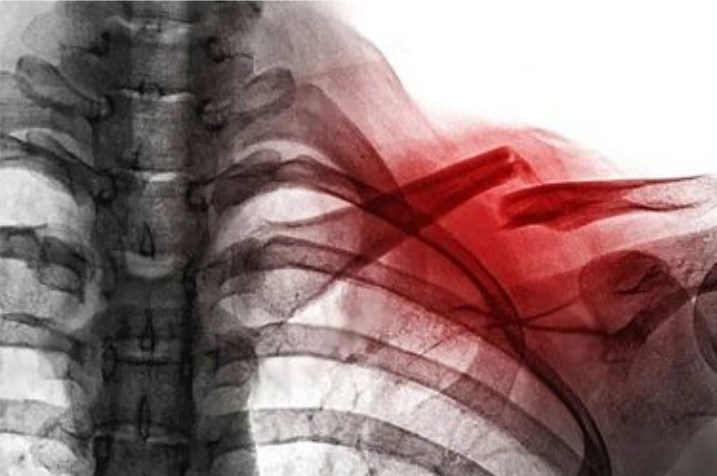

GÃY XƯƠNG ĐÒN